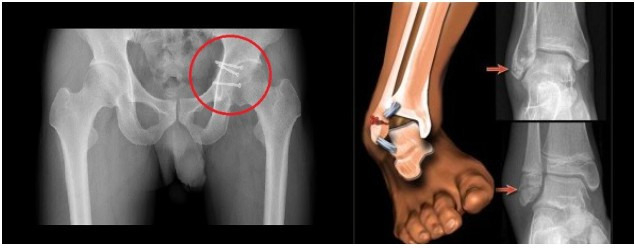

팔목골절 . 손목 골절.갈비뼈골절. 골반 골절. 고관절 골절.

골반 골절 , 발목 골절 빠른 회복을 위한 SAC 칼슘 복용 상담....

고관절 골절환자분 두분께 SAC칼슘과 어혈방 처방을 알려드렸고

손목골절 , 발목골절 , 골반 골절상을 입은분들께

70대 어르신분의 고관절 골절 상담을 말씀드려봅니다

이분은 골밀도가 T-3.5상태에서 고관절 골절을 당해

수술을 하시고 일주일만에 전화로 상담을 요청해오셔서

SAC 칼슘 하루 2회 복용과 어혈방 처방을 상담해드렸습니다